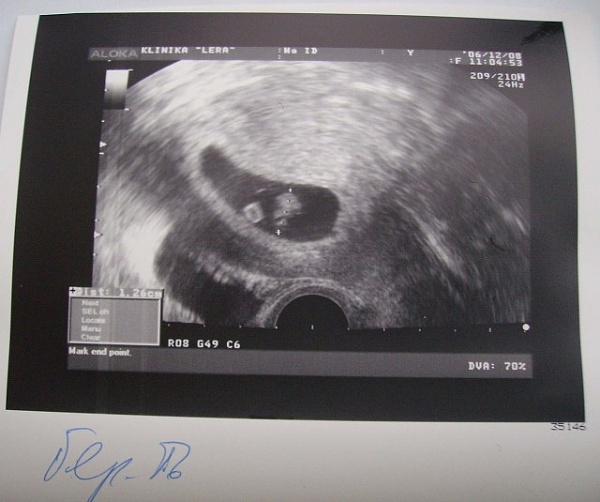

- Сам факт беременности – при помощи ультразвука удается увидеть на экране плодное яйцо в

полости матки. Проводить процедуру можно уже спустя 3-5 дней после предполагаемого зачатия, к этому времени яйцо достигает размеров порядка 2-3 мм. - Точный срок зачатия – также специалисту удается определить размер плода, иногда имеет место быть погрешность в 1-2 недели.

- Место расположения яйца-эмбриона – очень важно убедиться, что беременность началась правильно, внутриматочно, а не наоборот (это видно спустя 7-10 дней после появления задержки).

Наличие беременности, как факт. Плодное яйцо в полости матки определяется уже в это время.

Многие будущие мамы задаются вопросом, на какой неделе УЗИ покажет беременность. Современные аппараты позволяют это сделать примерно на 3-4 неделе, если используется влагалищный датчик (трансвагинальный метод). Если специалист проводит исследование через брюшную стенку (трансабдоминальный метод), то плодное яйцо он сможет обнаружить позже, на 5-6 неделе.На заметкуЗная, с какого срока УЗИ показывает беременность, можно не бежать на обследование сразу после задержки менструации. На очень маленьком сроке врач может и не увидеть плодное яйцо – и не потому, что его там нет, а так как аппаратура не совершенна. Не нужно создавать себе повод для тревоги – лучше подождать до 5-6 недель, когда будет хорошо видно плодное яйцо.